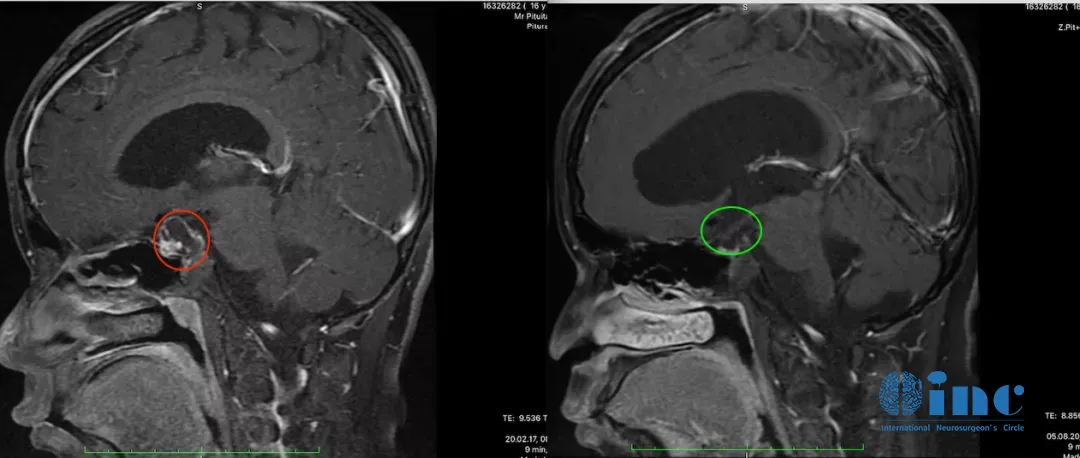

小杰的术前术后MRI对比,红色为术前肿瘤位置,绿色为术后切除效果